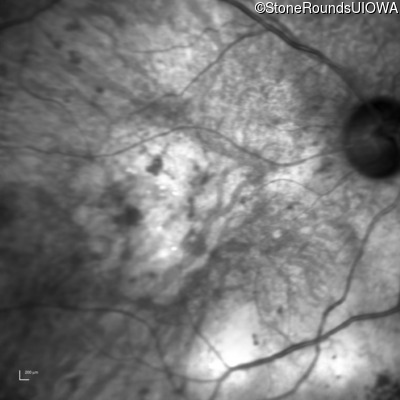

Infrared Fundus Photograph - Right - 1/200 sc

Exemplar